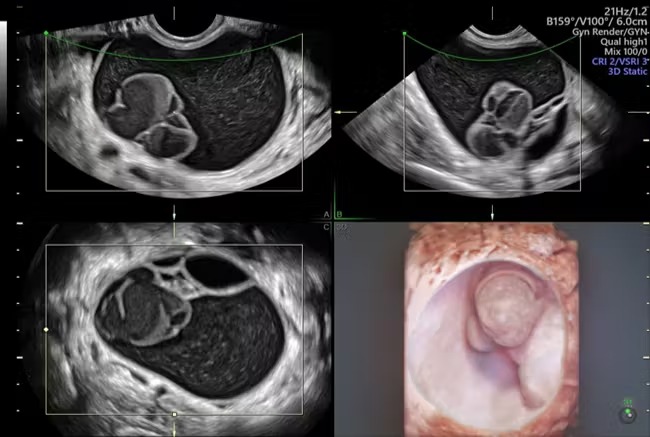

أظهرت الدراسات الحديثة أن الخلايا الموجودة في بطانة قناة فالوب، والتي كان يُعتقد أنها مصدر أكثر أشكال سرطان المبيض شيوعًا وعدوانية، يمكن أن تظهر تغيرات مبكرة مخفية قبل ظهور الأعراض أو الأورام المرئية.

وفي إحدى الدراسات، كانت المريضة تبلغ من العمر 22 عامًا، وتعاني من طفرات جينية نادرة تزيد بشكل كبير من خطر الإصابة بالسرطان مدى الحياة.

أظهرت صور المبايض وجود كيس حميد فقط، بينما كشفت الفحوص الخلوية العميقة عن تغيرات مبكرة تسبق ظهور السرطان.